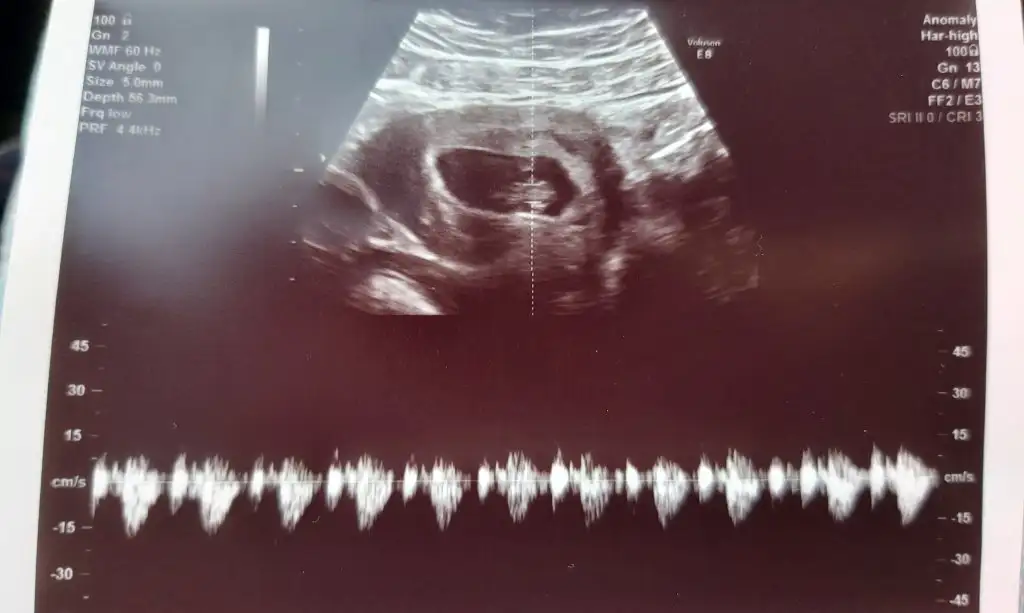

Rica etsem bana da bir tahmin de bulunabilir misiniz

Eklentiler

• 20200312_090552~2.webp

20200312_090552~2.webp

24,3 KB · Görüntüleme: 148

• 20200401_090222~3.webp

20200401_090222~3.webp

20,9 KB · Görüntüleme: 151